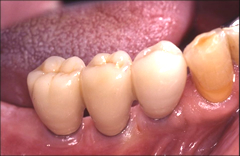

歯を製作するためにお口の中の型を取ります。製作した人工歯をアバットメント(支台部)に装着して完成です。